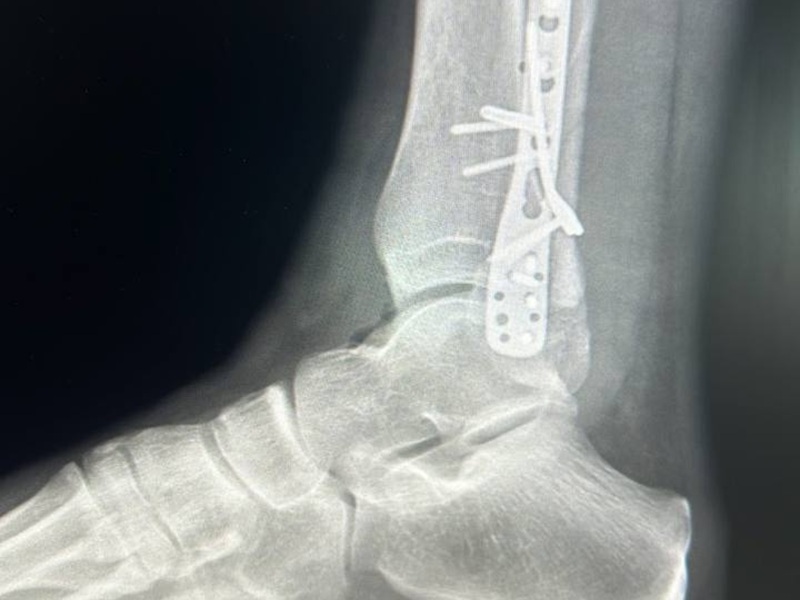

Металоостеосинтез МОС гомілки ДО-ПІСЛЯ